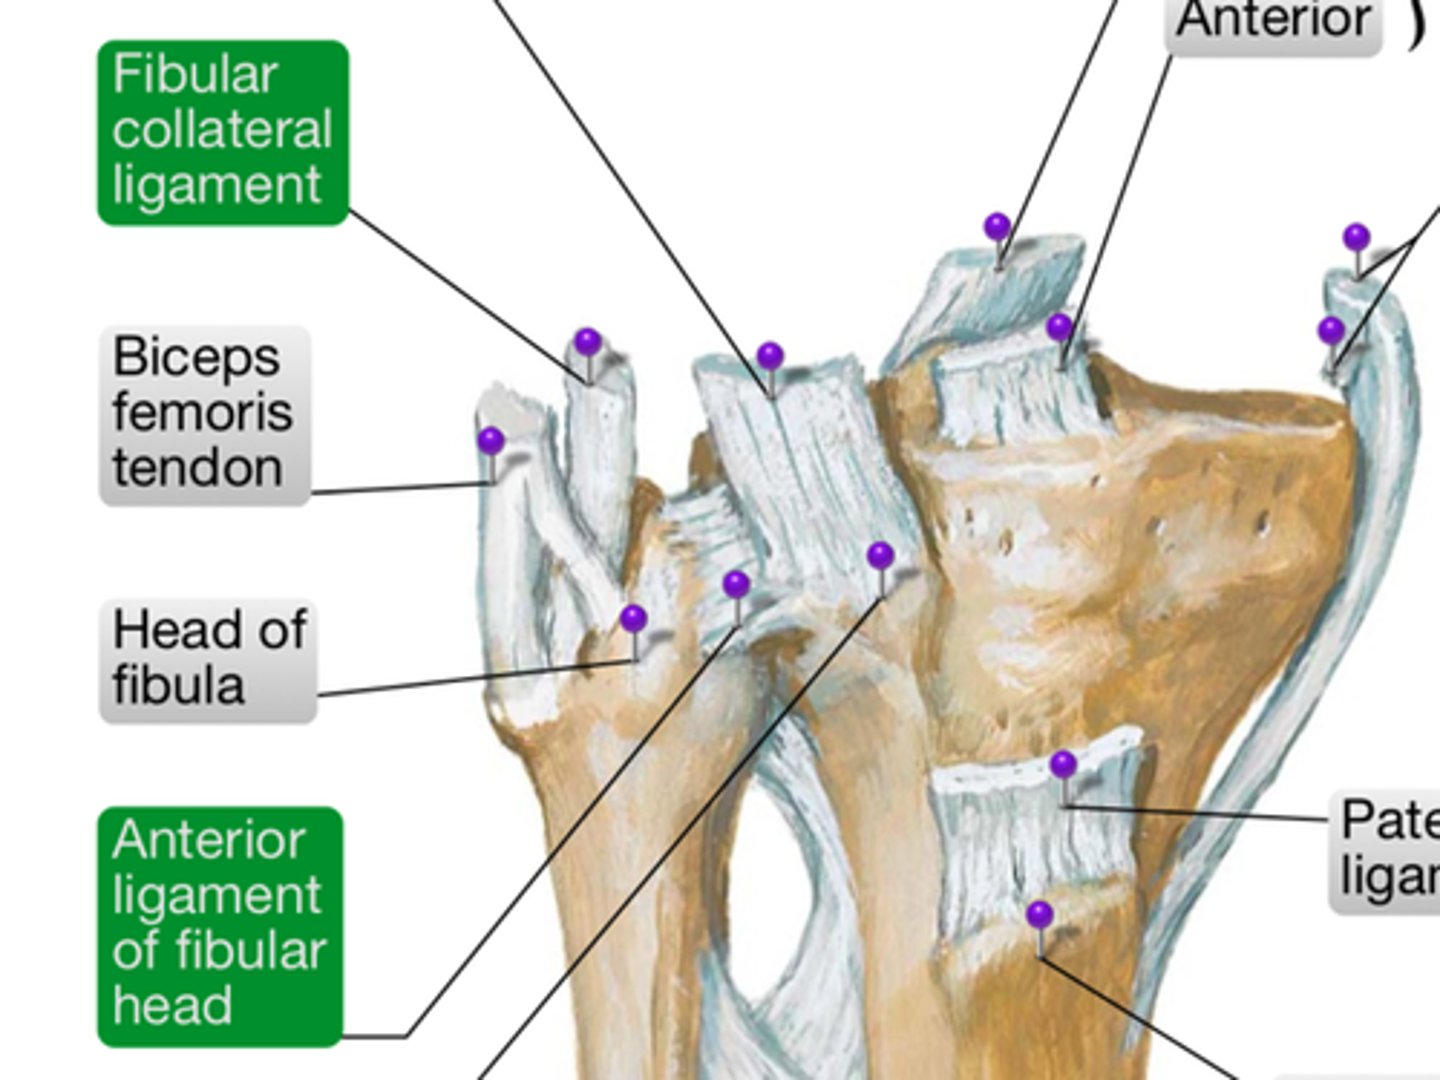

Stability for the proximal tibiofibular joint is provided by... (3 structures)

Ligaments

Joint capsule

Popliteus tendon